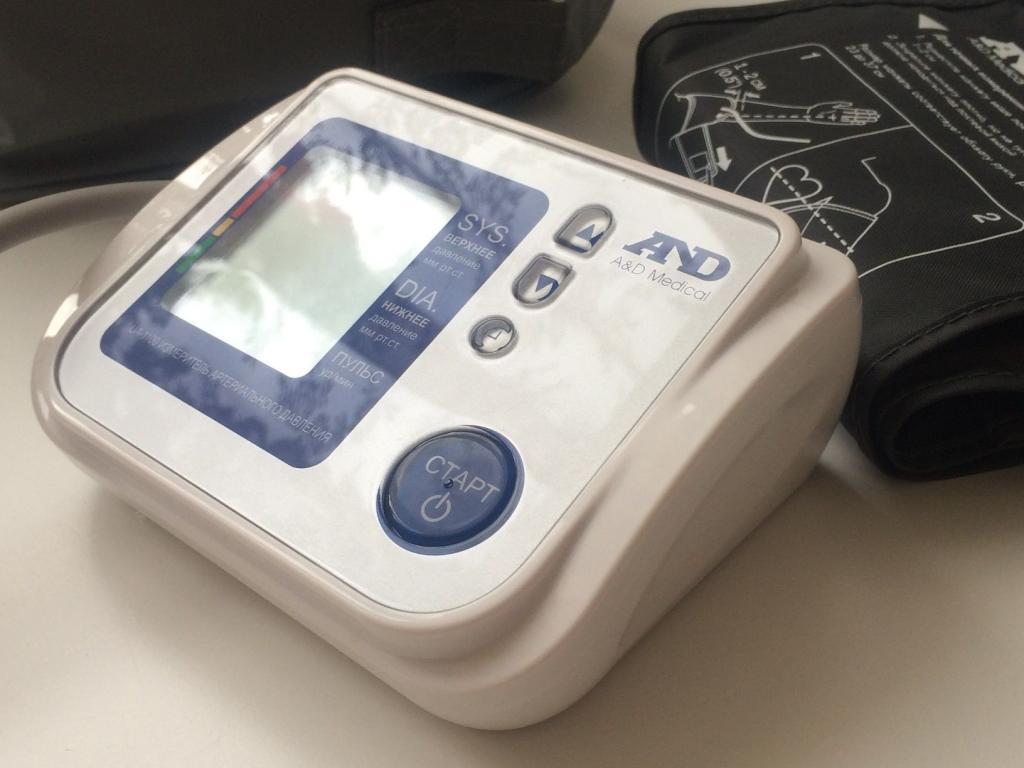

17.05.2023

Правила измерения артериального давления.

Неделя профилактики повышения артериального давления.

Подробнее...